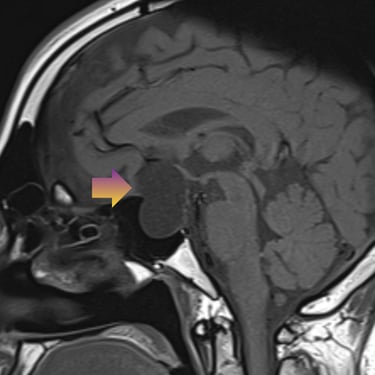

🧠Tumor selar quístico: abordaje mediante cirugía endoscópica transnasal (endoscopía selar).

Los tumores selares quísticos, como los adenomas hipofisarios quísticos o quistes de la bolsa de Rathke, pueden generar alteraciones visuales y hormonales. La cirugía endoscópica transnasal es una técnica mínimamente invasiva que permite el acceso seguro a la región selar, favoreciendo una resección eficaz con menor morbilidad.